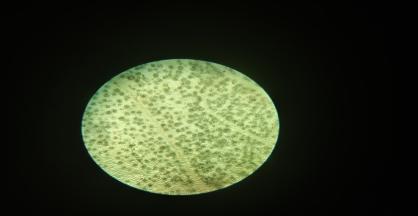

Fig. 1: Transverse section of leaves of Colocasia esculenta under 100x magnification scale

Fig. 2: The powder microscopy of leaves of Colocasia esculenta under 100x magnification scale